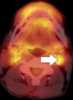

Necrotic lymph node metastasis

Lymphadenopathy or adenopathy is a disease of the lymph nodes, in which they are abnormal in size or consistency. Lymphadenopathy of an inflammatory type (the most common type) is lymphadenitis, producing swollen or enlarged lymph nodes. [Source: Wikipedia ]